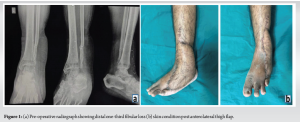

Here we report a case of 44-year-old male, a farmer by occupation, who presented to us with complaints of difficulty in weight bearing with ankle instability after he sustained a degloving injury over the lateral aspect of his left lower limb after being run over by a tractor 3 months back. At that time, he had a compound injury of the left ankle with distal fibula bone loss for which debridement of the necrotic tissue with an anterolateral thigh flap for wound coverage was done. On examination, the flap was present which was healed and accepted, the patient had significant mediolateral instability in the ankle and subtalar joint, varus opening, and antalgic gait with giving away sensation while walking. A plain radiograph of the ankle joint was ordered which showed complete loss of distal one-third of the fibula as shown in (Fig. 1). Basic blood investigations, chest radiograph, and pre-anesthetic work-up were performed. Pre-operative American Orthopaedic Foot and Ankle Society (AOFAS) score was 18/100 and the Foot and Ankle Disability Index (FADI) score was 26/104. Being a farmer, the patient wanted a stable, plantigrade, and pain-free limb for which arthroscopic ankle arthrodesis using an intramedullary tibio-talo-calcaneal nail was planned. In this case, the technique resulted in a stable, plantigrade, and pain-free limb, allowing for early mobilization without expected wound complications. At the 1-year post-operative follow-up as shown in the last figure, there was a notable improvement in clinical and functional outcomes, as evidenced by significant increases in AOFAS and FADI scores.